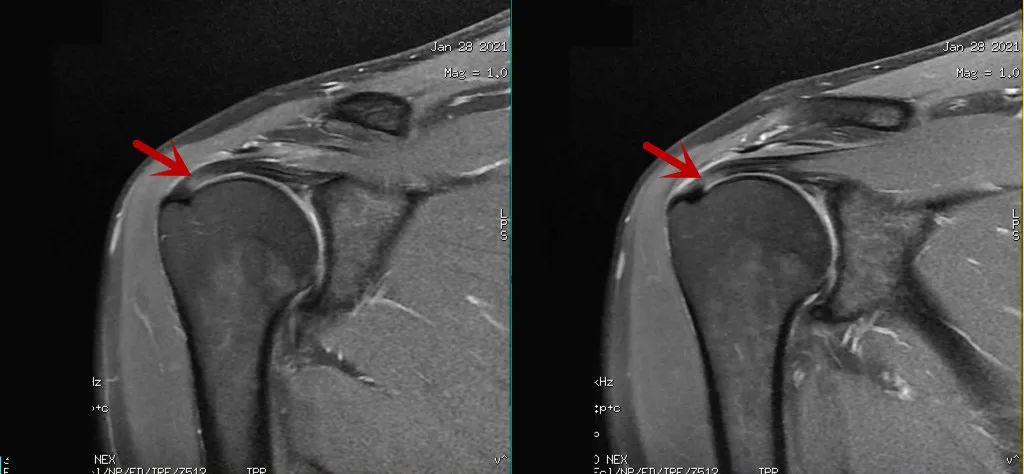

在肩关节冠状面的成像中,如采用短TE的的序列(如T1WI、PDWI)成像时,其魔角效应较明显,以PDWI序列最为显著,图△箭,所以对于肩关节的冠状面成像建议采用长TE的T2WI序列扫描。